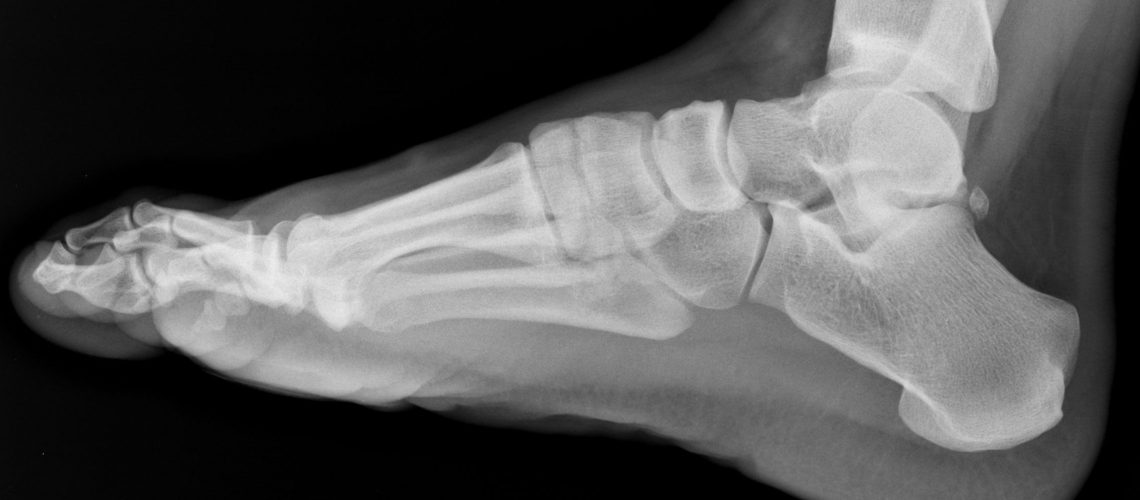

ankle X-ray

Have you ever twisted your ankle and wondered if you should get an x-ray to see if it is broken? Therapists use The Ottawa Ankle Rules to determine whether or not an x-ray is indicated after spraining your ankle. An x-ray is indicated if there is specific pain at certain bony sites at the ankle which are more prone to being fractured after an injury. These rules apply whether you twisted your ankle inwards or outwards.

An ankle and foot x-ray are required if there is:

Pain in the Malleolar or Midfoot Zones on either the inside and outside portion of the ankle

A: Pain at the lateral malleolus (outside of the ankle) and about 6 cm up the fibula

B: Pain at the medial malleolus (inside of the ankle) and about 6 cm up the tibia

C: Pain at the bony prominence (5th metatarsal) on the outside of your foot

D: Pain at the bony prominence (navicular) on the inside of your foot